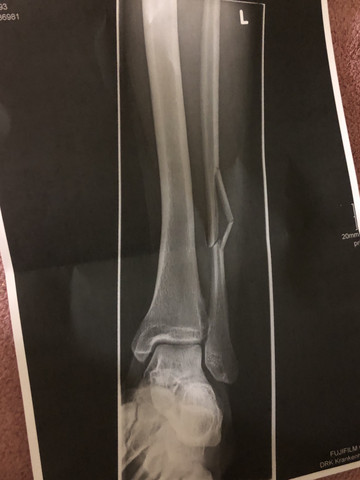

Chronik Einer Sprunggelenkfraktur Sky Junkies